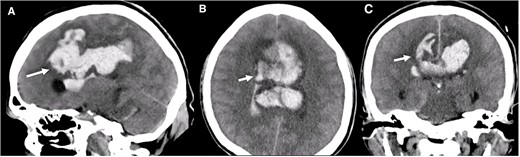

A multislice computed tomography (CT) without contrast revealed an extensive interhemispheric hematoma in the frontoparietal region, subarachnoid hemorrhage, and intraventricular hemorrhage in the adjacent area (Fisher grading score of IV) (Fig. 1). In addition, cerebral angiotomography and 3D reconstruction imaging suggested the presence of two abnormal vascular lesions: (i) a fusiform aneurysm of 12 × 7 mm in an accessory A2 portion of the ACA and (ii) an unruptured saccular aneurysm of 3.3 × 2.8 mm in the distal segment of the basilar artery adjacent to the anterolateral surface of the P1 segment and the left superior cerebellar artery (Figs 2 and 3).

Brain CT without contrast shows a large interhemispheric hematoma, intraventricular hemorrhage, and subarachnoid hemorrhage (white arrows) in (A) Sagittal, (B) Axial, and (C) Coronal views.